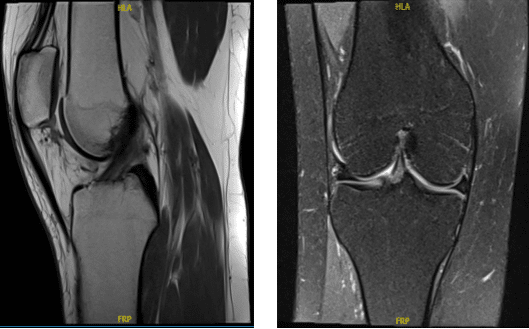

The MRI was reviewed and discussed; for her right knee pain it has no fracture, dislocation, marrow replacement process, or osteochondral lesion is identified.

The distal quadriceps tendon, patella, and patellar ligament appear within normal limits. 0.6 x 0.9 x 1.7 cm lobular oval lesion that is low signal on TI and heterogeneous signal on T2 is identified between the lateral patellar facet and anterior femur in the patellofemoral joint region and may represent fibrotic changes.

The anterior cruciate ligament, posterior cruciate ligament, medial collateral ligament, and lateral collateral ligament are intact. No soft tissue mass or abnormal signal in the musculature is identified. An oblique tear in the posterior horn of the medial meniscus is identified. The lateral meniscus is intact with no tear identified.

With impression of Oblique tear in the posterior horn of the medial meniscus. 0.6 x 0.9 x 1.7 cm lobular oval lesion that is low signal on TI and heterogeneous signal on T2 is identified between the lateral patellar facet and anterior femur in the patellofemoral joint region and may represent fibrotic changes.

MRI showed lesion in the lateral margin of the patella as well as medial meniscus tear. We discussed treatment options and opted for surgical management. We discussed the risks and benefits including infection, bleeding, injury to adjacent nerves and vessels, inability to heal, need for repeat surgery, need for rehabilitation amongst others.

MRI Right knee non-contrast